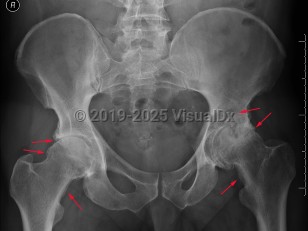

Osteomyelitis

Reactive arthritisReactive arthritis

ScurvyScurvy

Psoriatic arthritisPsoriatic arthritis

Rheumatoid arthritis

Septic arthritisSeptic arthritis

Systemic lupus erythematosusSystemic lupus erythematosus

Calcium pyrophosphate deposition diseaseCalcium pyrophosphate deposition disease

GoutGout

Avascular necrosis